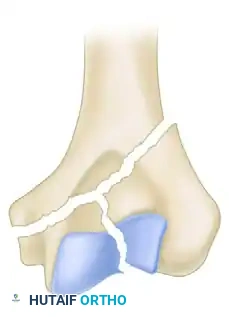

Illustration of an isolated lateral condylar fracture.

Fixation of the lateral condyle utilizing a lag screw and a contoured mini-fragment buttress plate.